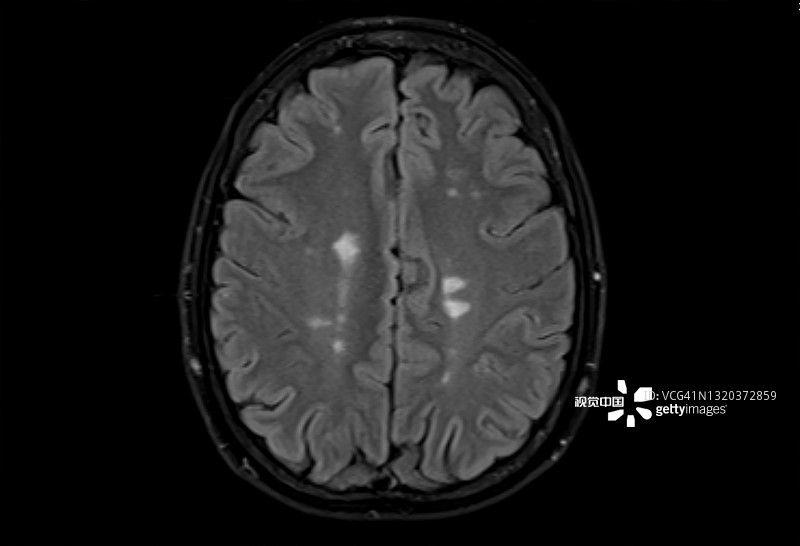

多發(fā)性腦硬化癥的磁共振成像,軸位Flair視圖

多發(fā)性硬化癥 (MS)MS是一種中樞神經(jīng)系統(tǒng) (CNS) 的慢性自身免疫和炎癥性疾病。MS與免疫系統(tǒng)介導(dǎo)的自身反應(yīng)性T細(xì)胞和B細(xì)胞對神經(jīng)元髓鞘的攻擊有關(guān),導(dǎo)致脫髓鞘并最終導(dǎo)致神經(jīng)元丟失。由于中樞神經(jīng)系統(tǒng)中神經(jīng)變性和斑塊的形成,MS患者會根據(jù)斑塊的位置經(jīng)歷特定的神經(jīng)功能障礙。例如,視神經(jīng)中的斑塊會導(dǎo)致視力喪失。